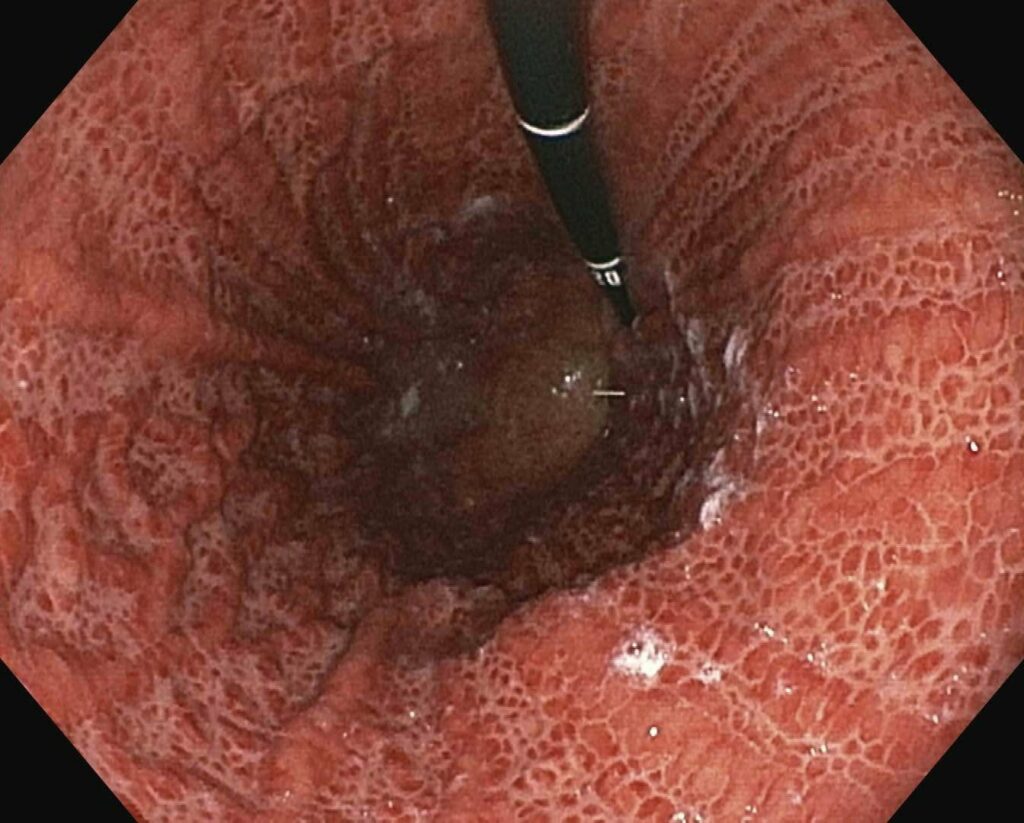

As alterações da gastropatia hipertensiva portal são mais evidentes na mucosa do corpo e fundo do estômago. Os aspectos endoscópicos incluem um padrão de eritema fino, difuso e pontilhado, rash escarlatiniforme ou o padrão conhecido como “pele de cobra” ou “mosaico”, onde se observa áreas avermelhadas, pequenas e poligonais delimitadas por bordas deprimidas e amarelo claras5-8. A gastropatia severa é caracterizada pela presença de pontos vermelho escuros ( “cherry red spots” ) e áreas de hemorragia mucosa difusa ( “gastrite hemorrágica” )5,8. Em estudos endoscópicos com grande amostragem de cirróticos assintomáticos, mais que 50 % apresentam sinais de gastropatia hipertensiva portal, sendo o achado mais comum o padrão mosaico ou em pele de cobra no estômago proximal8,9.

Em 1994, o NIEC (New Italian Endoscopic Club) propôs nova classificação para padronizar as descrições da gastropatia hipertensiva portal10. A classificação se baseia em 4 sinais endoscópicos elementares (tabela 2).

| Classificação da gastropatia hipertensiva portal (Milão –1994) |

| 1. Padrão mosaico ( mosaic-like pattern – MLP ), graduado como leve, moderado ou severo |

| 2. Marcas vermelhas ( red marks – RM ), que incluem lesões puntiformes vermelhas ( red point lesions – RPL ) e pontos vermelho cereja ( cherry red spots – CRS ) |

| 3. Pontos marrom escuros ( black Brown spots – BBS ) |

TRATAMENTO